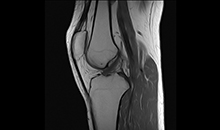

亚秒级

快速智能匀场技术

能在1秒内完成对任意部位,任意区域的快速精准匀场。磁场均匀度可达0.002ppm。在极速匀场过程中,几乎不受运动伪影的影响。